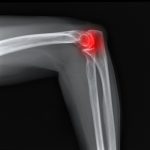

Shoulder pain represents an enormous burden on society with up to 16% of the population suffering from shoulder pain in any given month. Furthermore, just 50% of shoulder injuries will recover inside a month, meaning that there is a high rate of lingering pain and dysfunction.

In this radio interview you will discover answers to the following 10 frequently asked questions that relate to the management and diagnosis of shoulder pain and physiotherapy: